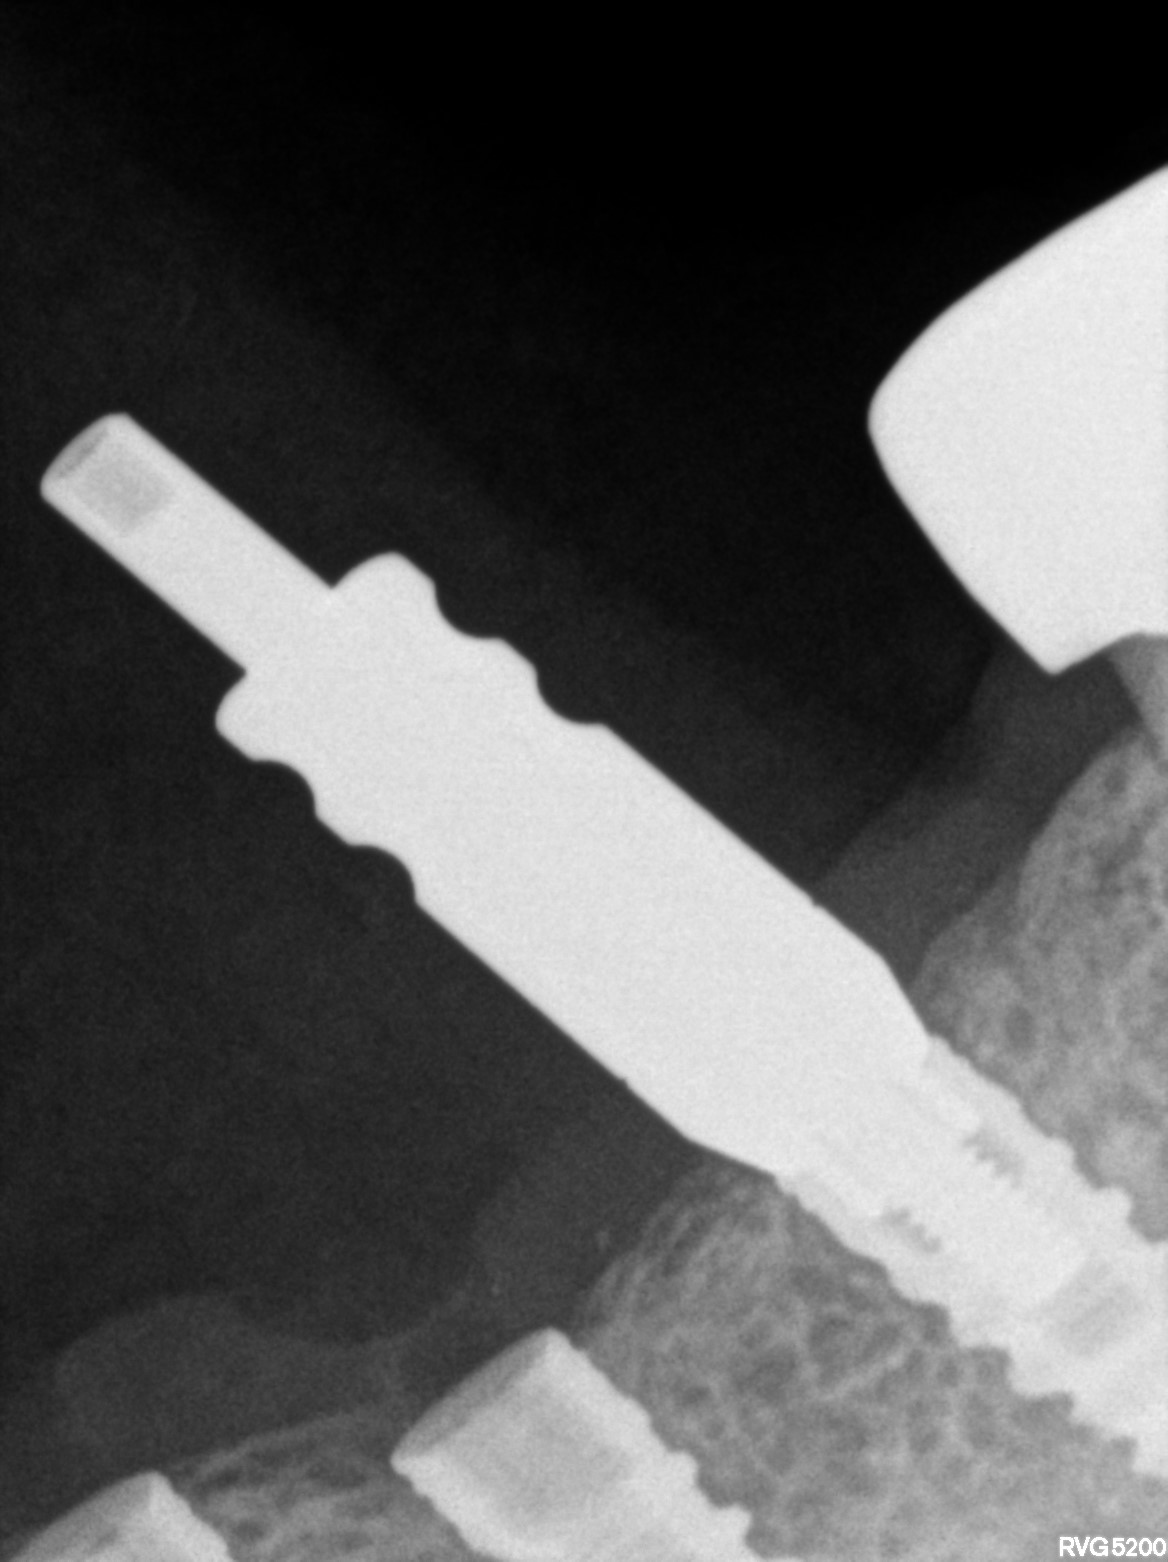

Dental Radiographs FHIR: DocumentReference · LOINC 24641-7

R55.jpg

24641-7